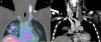

Tromboflebitis séptica yugular por Streptococcus viridans

Septic thrombophlebitis caused by viridans group Streptococci